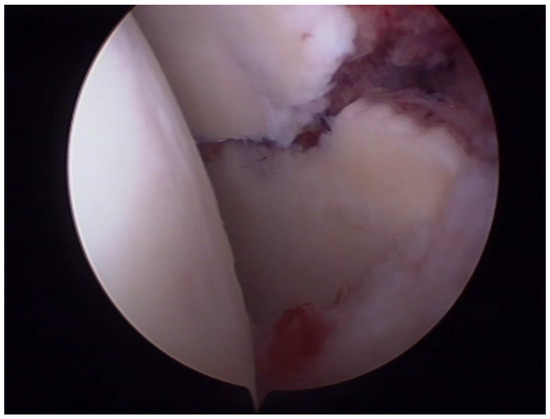

6.1. Ideberg Type III Fractures

- Tao, M.A.; Garrigues, G.E. Arthroscopic-Assisted Fixation of Ideberg Type III Glenoid Fractures. Arthrosc. Tech. 2015, 4, e119–e125. [Google Scholar] [CrossRef] [PubMed]

- Acharya, P.; Arora, B.; Pinto, N. Arthroscopy Assisted Percutaneous Fixation of Ideberg Type Iii Glenoid Fractures. J. Orthop. Case Rep. 2015, 5, 41–43. [Google Scholar] [CrossRef]

- Yang, H.B.; Wang, D.; He, X.J. Arthroscopic-assisted reduction and percutaneous cannulated screw fixation for Ideberg type III glenoid fractures: A minimum 2-year follow-up of 18 cases. Am. J. Sports Med. 2011, 39, 1923–1928. [Google Scholar] [CrossRef] [PubMed]

- Bonczek, S.J.; Hutchinson, R.; Chakravarthy, J. An innovative method of fracture reduction in an arthroscopically assisted cannulated screw fixation of an Ideberg type III glenoid fracture. Int. J. Shoulder Surg. 2015, 9, 56–59. [Google Scholar] [CrossRef]